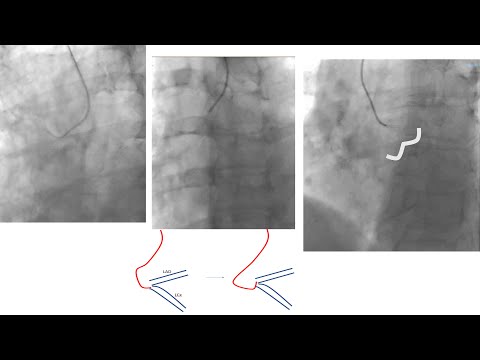

5.7 Manual of PCI - How to manipulate catheters to engage via femoral access

Left+right coronary engagement for general fellows: step-by-step tips, diagrams, caveats (5 for RCA)

Grafts engagement (femoral+radial): detailed steps, diagrams, troubleshooting, and videos- SVG+LIMA